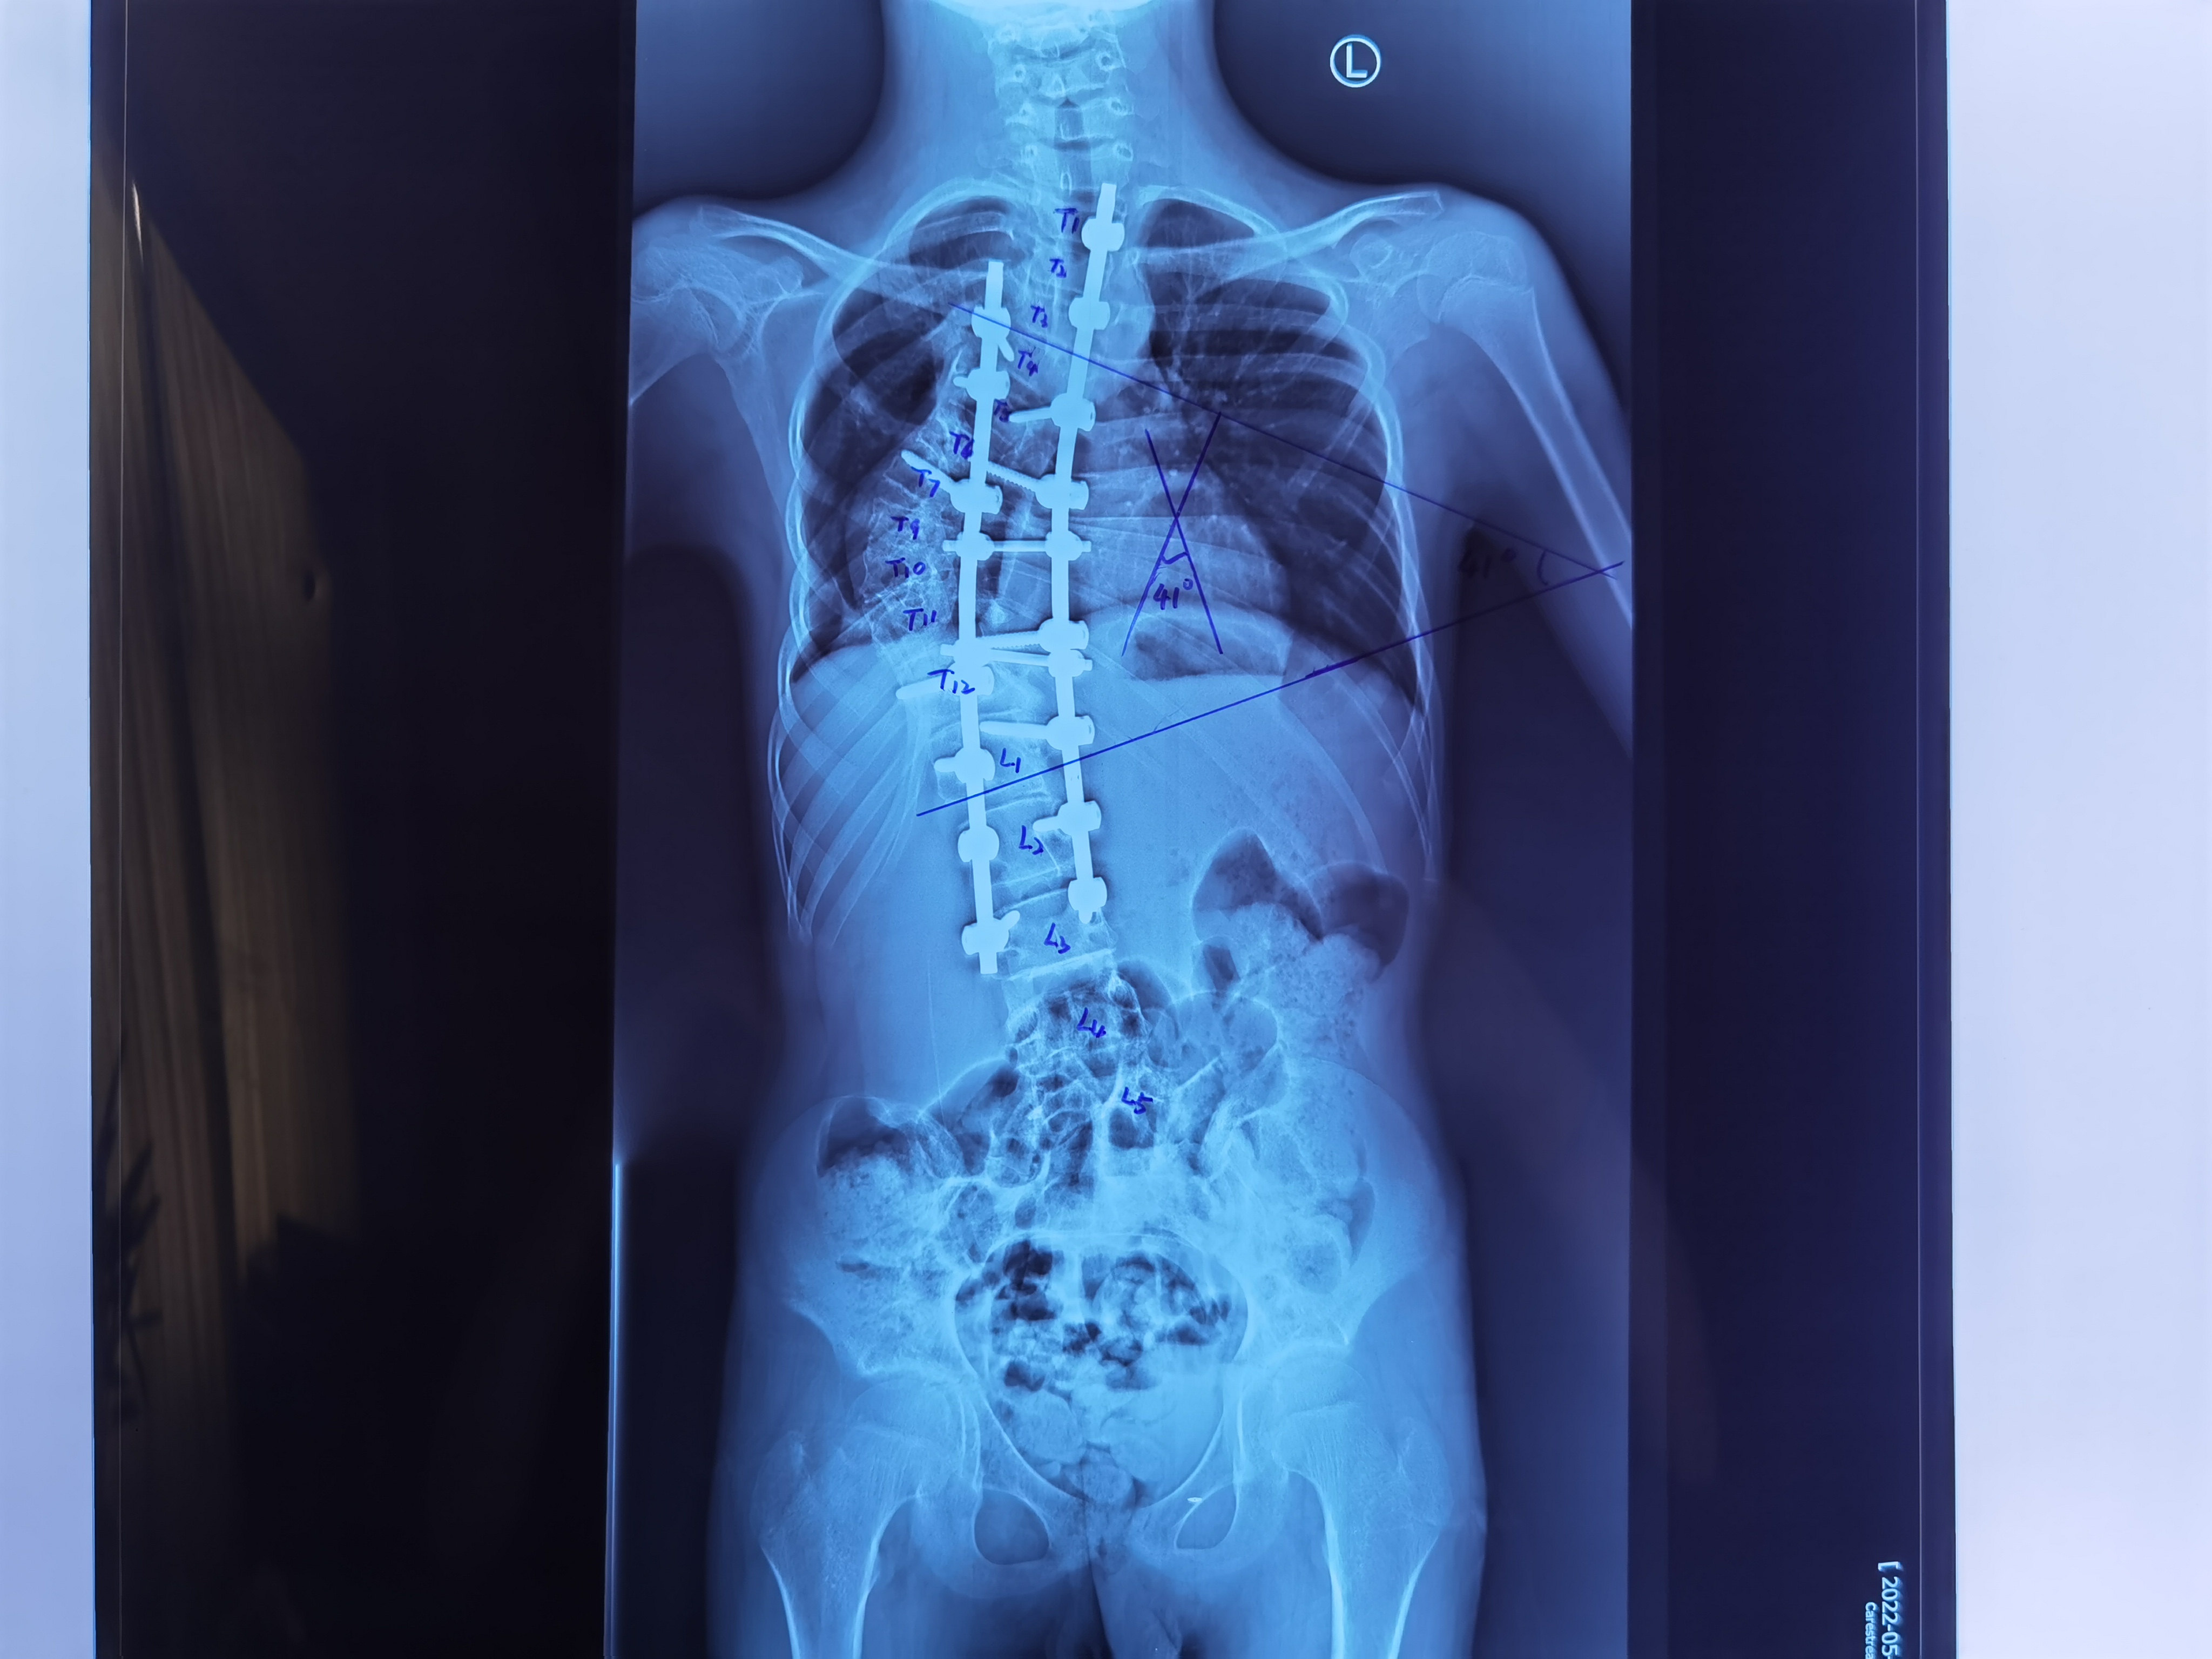

手术前

“通过术前术后的X光片对比可以看出,手术非常成功。”陈主任说。术前X光片显示脊柱以胸椎为中心向右侧呈明显侧弯畸形,侧弯角度COBB’S角为124度。右肩高,左肩低,骨盆倾斜,左侧骨盆高于右侧。术后X光片显示脊柱侧弯畸形得到明显的改善,脊柱侧弯角度COBB’S角为41度,较术前矫正了83 度,双肩部基本平齐,双侧骨盆基本平齐。